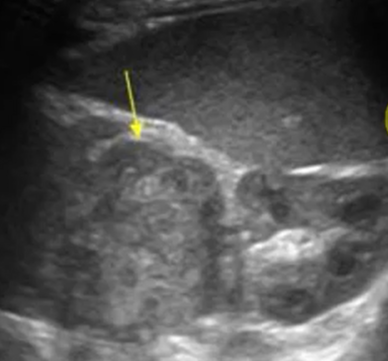

What is the typical sonographic appearance of a neuroblastoma?

Heterogeneous, hyperechoic mass with poorly defined margins

What is being evaluated on a FAST scan if the transducer is in the RUQ area?

Morison's pouch